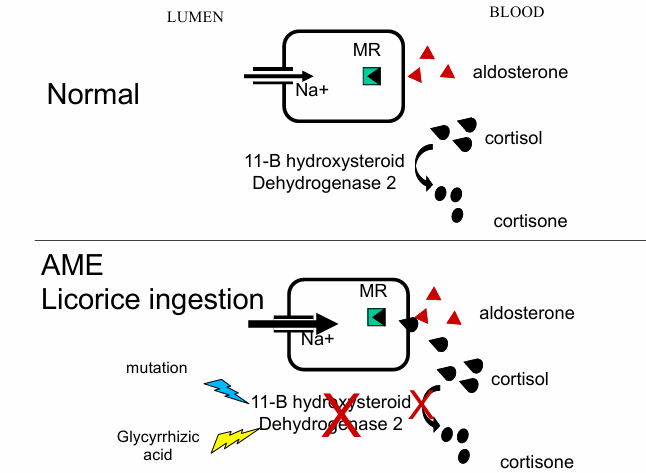

normal v. AME for lumen to blood

normal v. AME with licorice ingestion for lumen to blood